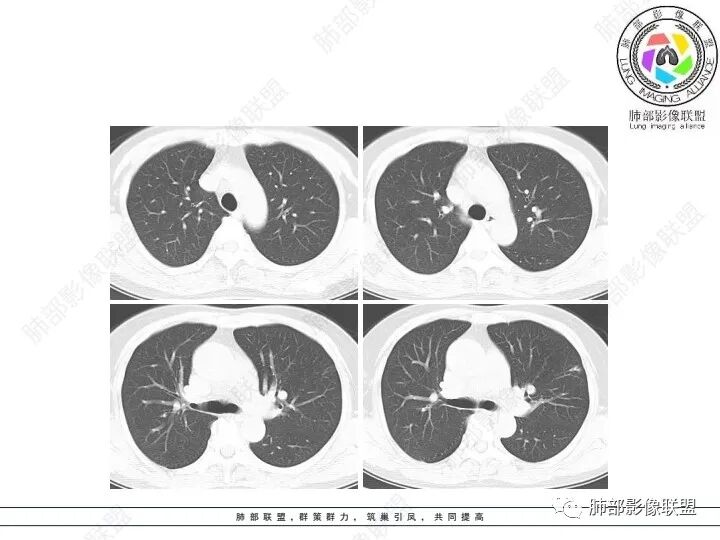

1、临床特点:61岁女性,体检发现肺结节。

2、影像特点:左肺上叶不规则病灶,冠状位、矢状位、斜状位重建显示病 灶整体沿着支气管方向呈斑片状,多结节堆积感明显,病灶大部分边缘显示平直,局部边缘稍膨隆,边界显示比较清楚,近端支气管壁显示增厚,周围可见长索条影及多发结节影,未显示典型“树芽征”。邻近叶间裂未受牵拉凹陷。纵隔窗显示病灶中央可见点状高密度钙化影。

3、病例小结:老年女性体检发现肺部结节,缺乏临床表现,需要警惕恶性。结合影像特点,左肺上叶病灶整体缺乏膨隆感,边缘大多平直,周围多发卫星灶(可见多发长索条影、并非肺CA的细短毛刺),病灶收缩力很弱(邻近叶间裂未见明显凹陷),观察1mm重建图亦可以发现病灶周围没有边界清楚的GGO,病灶内可见钙化点,肺门纵隔未见肿大淋巴结。综合以上,此病灶首先考虑炎性,结核可能性大,有条件可以增强扫描,有助于我们进一步判断。